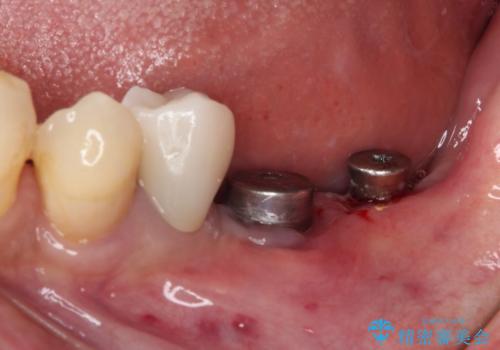

- 一度治療を終えたものの、奥歯へインプラントの追加を希望された患者様です。

最後臼歯部にインプラントを1本追加埋入し、2歯連結のクラウンにて補綴治療を行うこととしました。